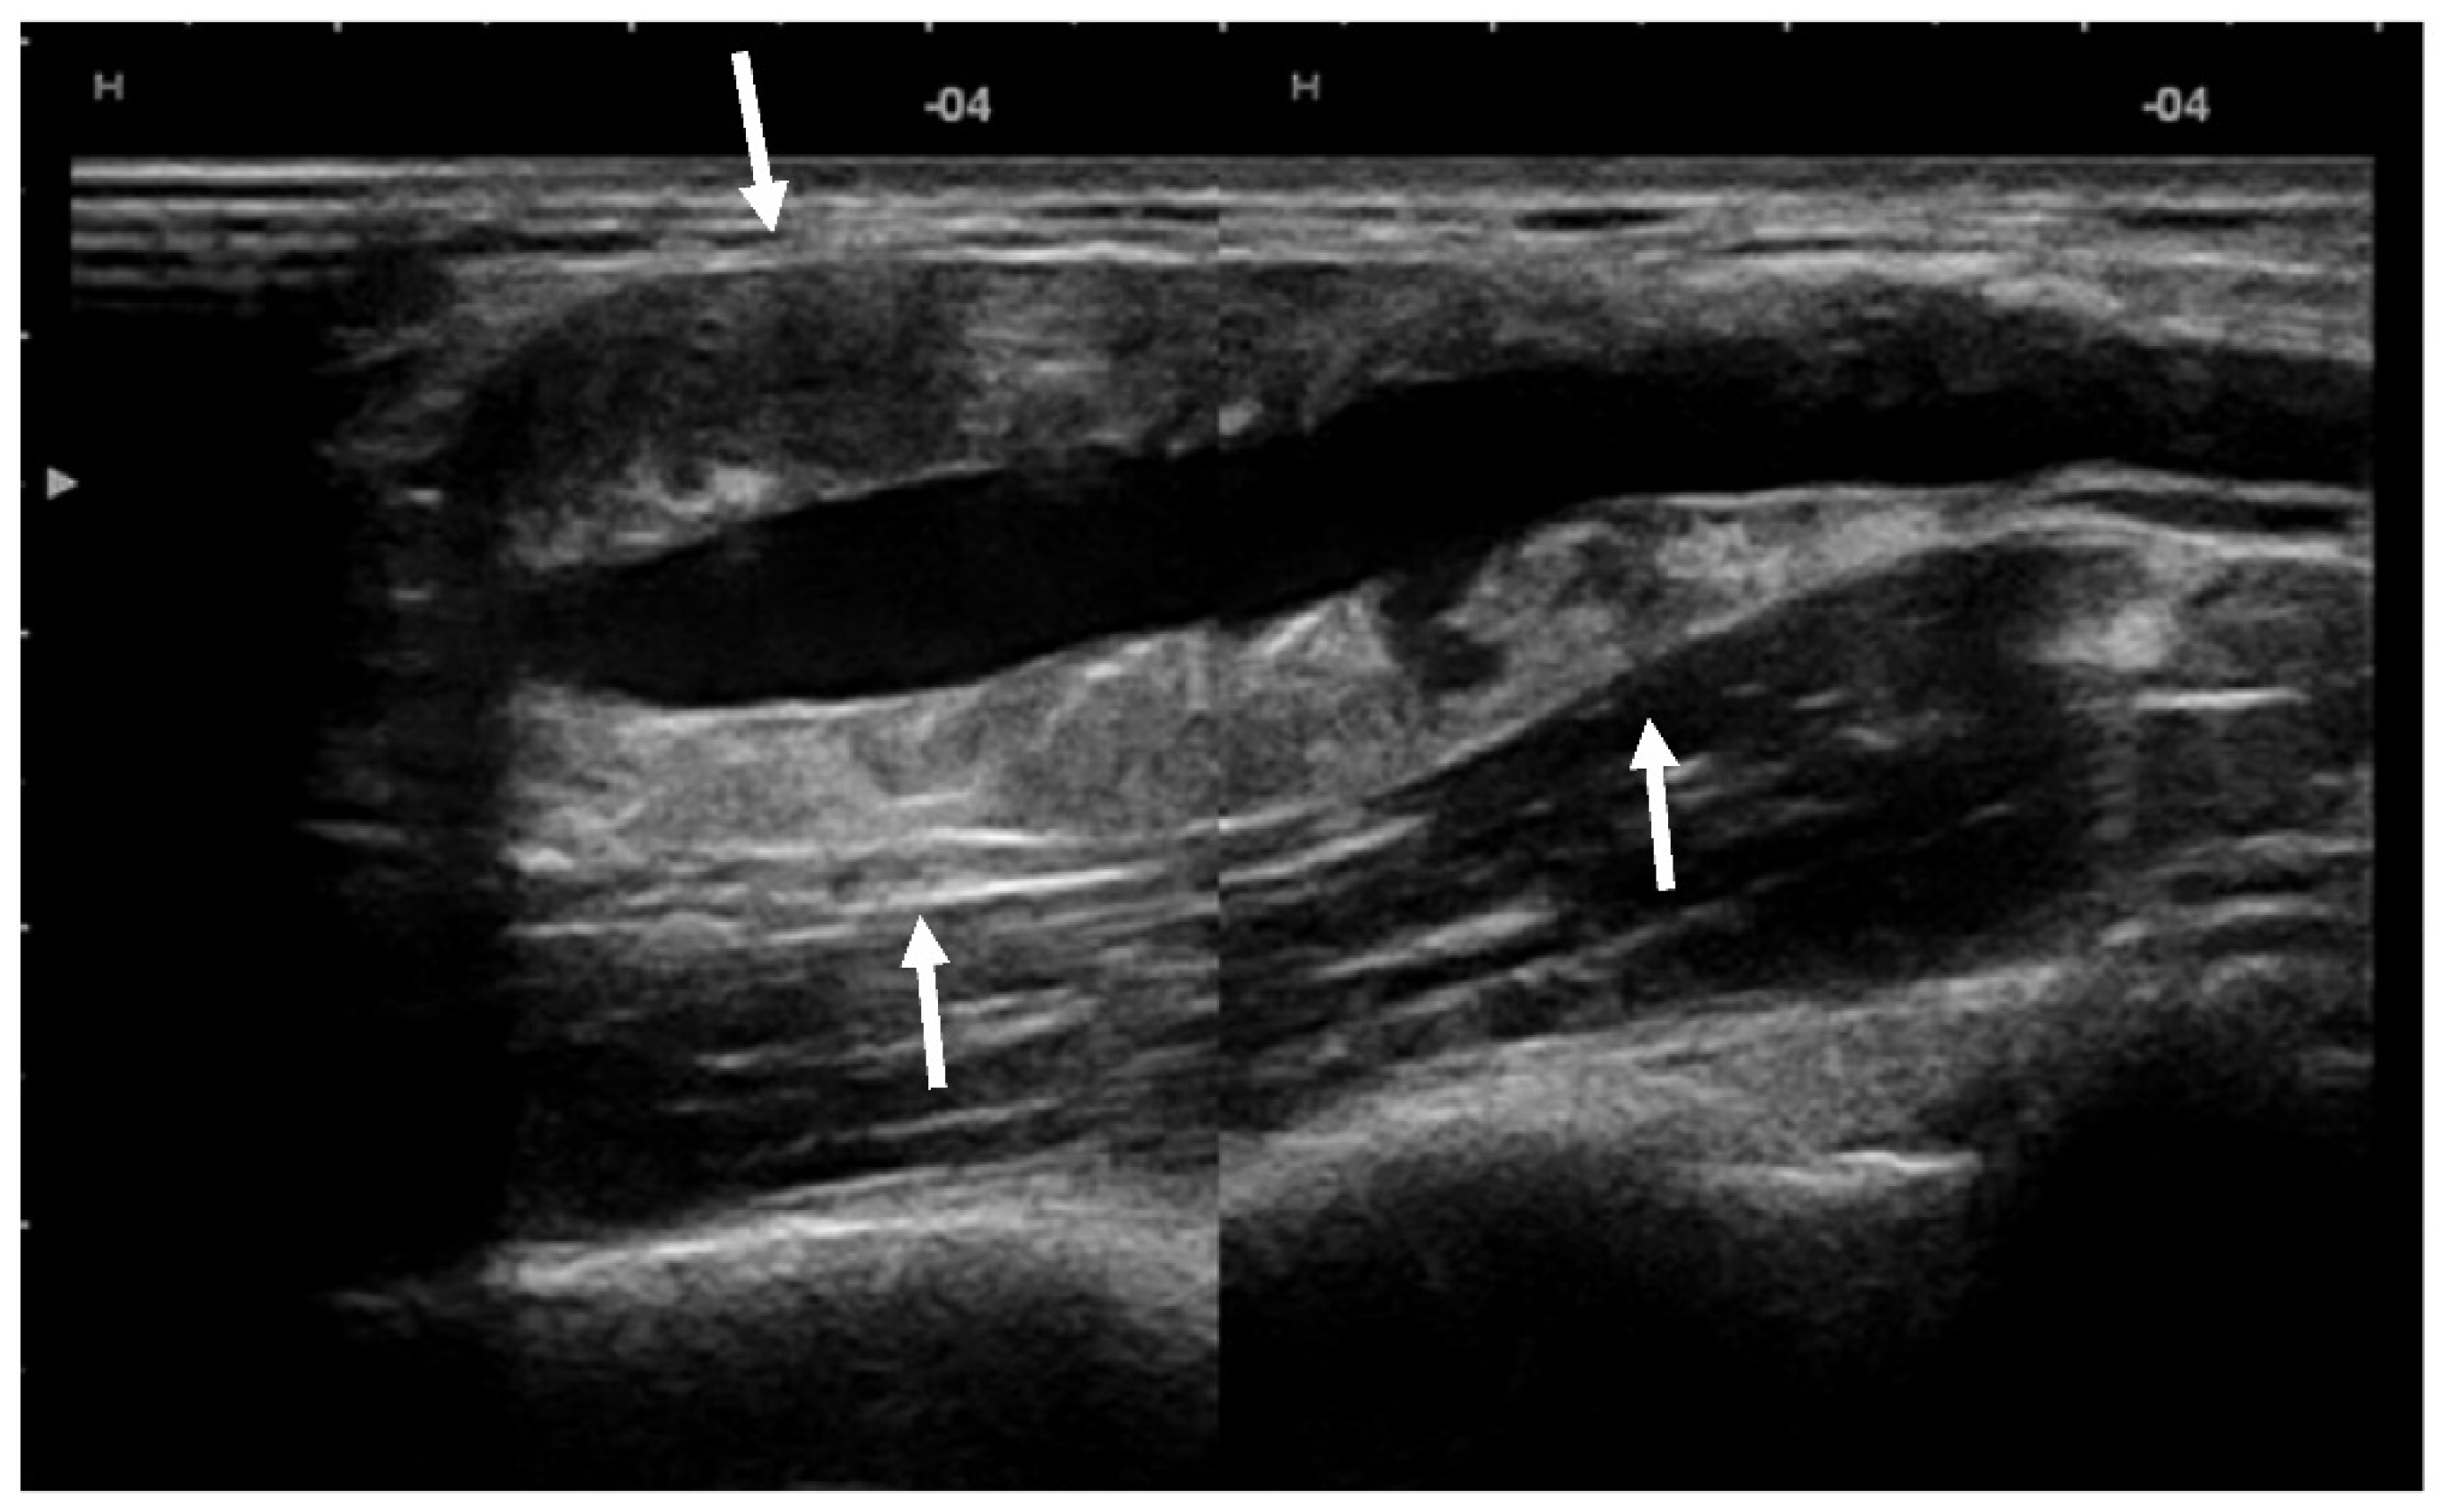

US showed a solid mass surrounding the brachial artery, located in the arterial wall, with a clear delimitation between the internal and external wall of the artery (Figure 2). The mass was encasing the artery’s lumen without stenosis at Doppler US (Figure 3A). The brachial vein and nerve were situated nearby without evident signs of tumor invasion nor growth around them. The solid mass had internal vascularity, with a small nutritive vessel originating from the brachial artery (Figure 3B).

Figure 2.

US showed a solid mass (arrows) located within the brachial artery wall, encasing the vessel.